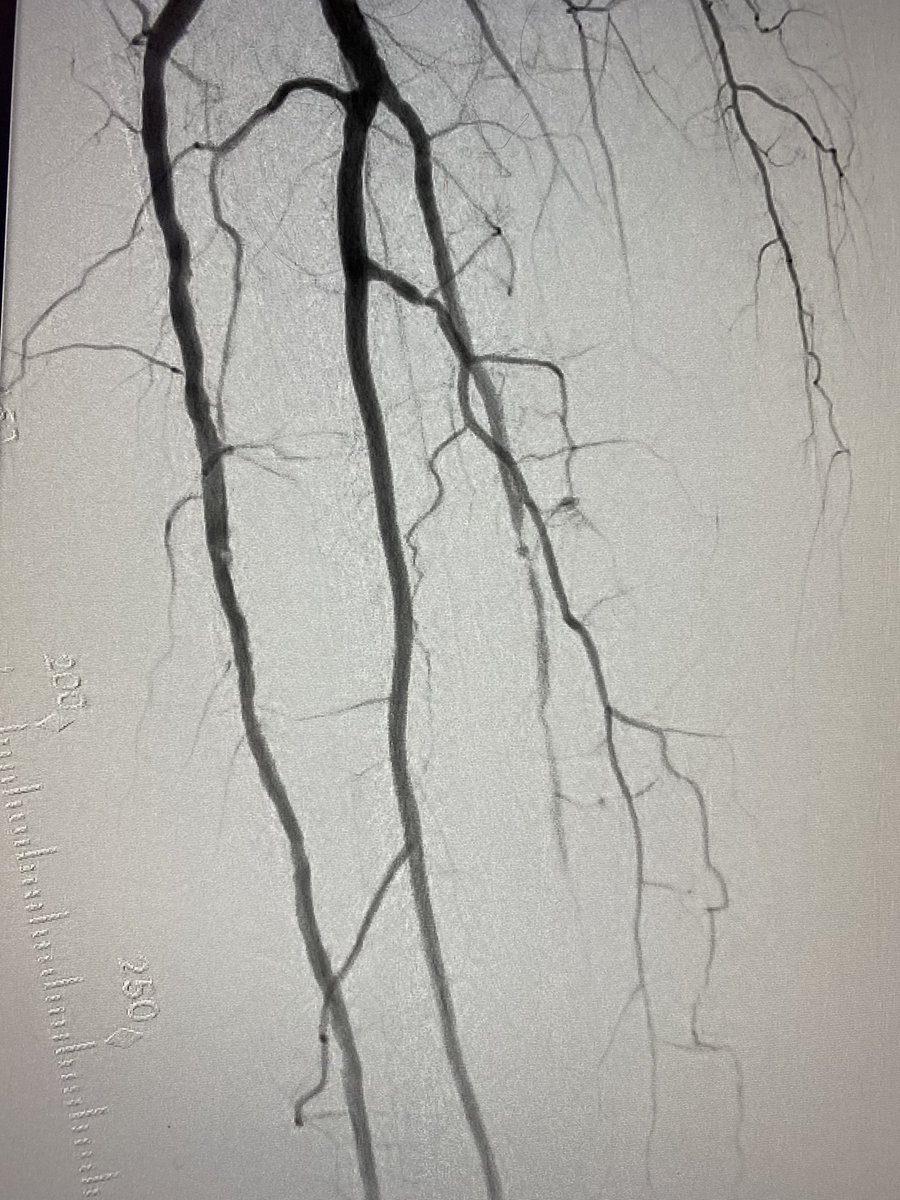

R5 CLI patient. Around the loop to cross PT/plantar CTO (retrograde).

#pad#clipic.twitter.com/wZind2xyvP